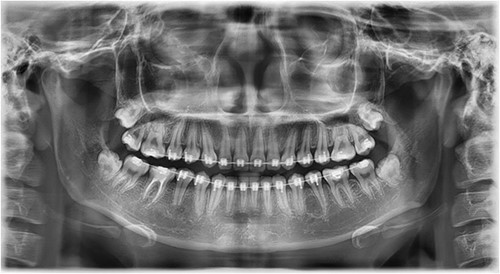

A 21-year-old patient with a non-contributory history reported to the clinic with a complaint of spacing in the anterior teeth. On radiographic examination, eumorphic supernumerary premolar crowns were found located between the roots of the mandibular first and second premolars (Fig. 1). The patient was completely asymptomatic and had no knowledge regarding the presence of these accessory teeth.

Image depicting the supernumerary premolar buds located between the first and second mandibular premolars.